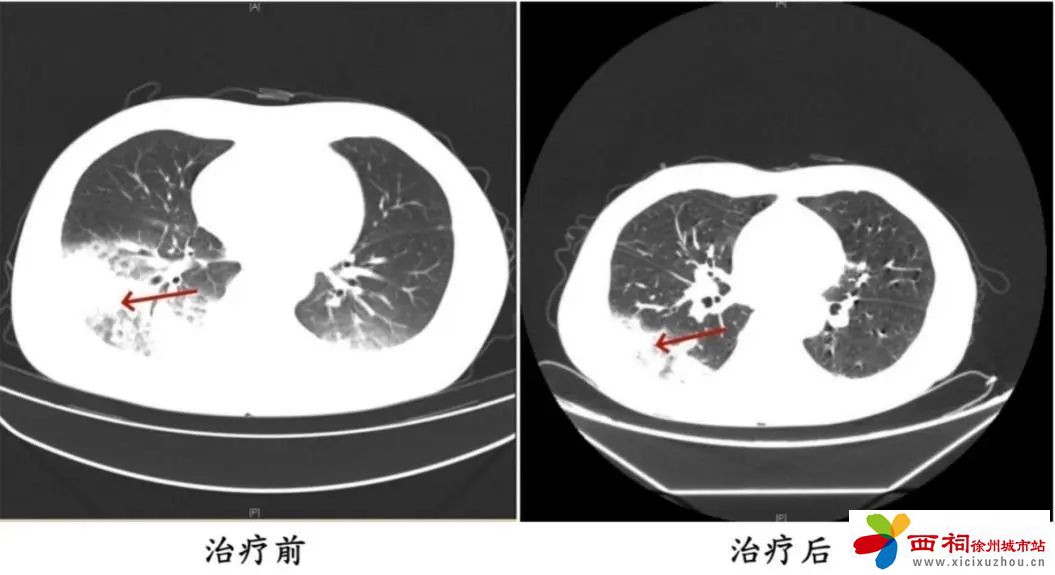

据了解,周先生此前驾车出差。因为天气热,他启动了久未清洗的车载空调,每天在车上的时间超过十个小时,回来后就出现了发热、咳嗽等类似“感冒”的症状。医生判断患者有可能感染了军团菌,进一步检测结果显示:嗜肺军团菌,明确诊断为军团菌肺炎。医生马上调整治疗方案,改用可覆盖嗜肺军团菌的一线用药抗感染,患者体温逐渐下降,次日体温恢复正常,经过后续治疗康复出院。

周先生治疗前后的肺部CT影像